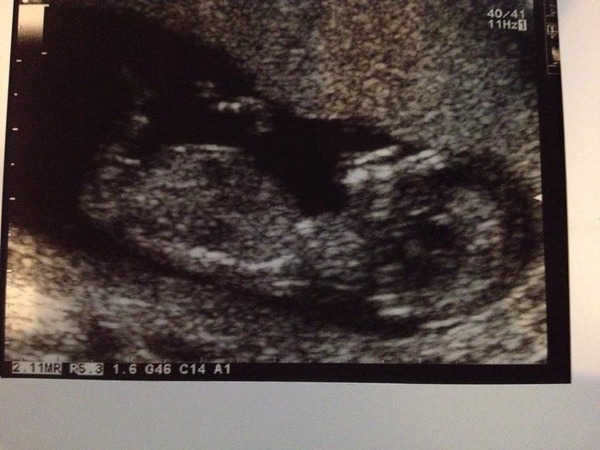

littleluna89 · 03/10/2014 00:13

So we opened the box! I refused to look at the screen till the lady promised me there was a heart beat might have had a small melt down before going in after I remembered my 36 week scan with miniLuna, mrLuna all but had to march me in everything is fine, we have just the one and I've been put forward to 12+5 with a due date of 11th April. It's a bit of a giggle really as we got my cousins 'save the date' card through for their wedding pretty much the week we started trying for this bump and that's the date they told us to save! all be it for their wedding not a day in the hospital!!

The consultant was all full of action plan, and he's the same consultant we had last time (all be it slightly less hands on last time) so we'll know on 19th March whether they're going to let bump carry on cooking or start me on steroids in preparation for evicting bump. We've got extra scans at 28, 32 and 26 weeks, the midwife is seeing us for all the normal appointments plus the 1st baby appointments so she can keep a close eye too and my anaesthetic review will hopefully be scheduled for some time soon!